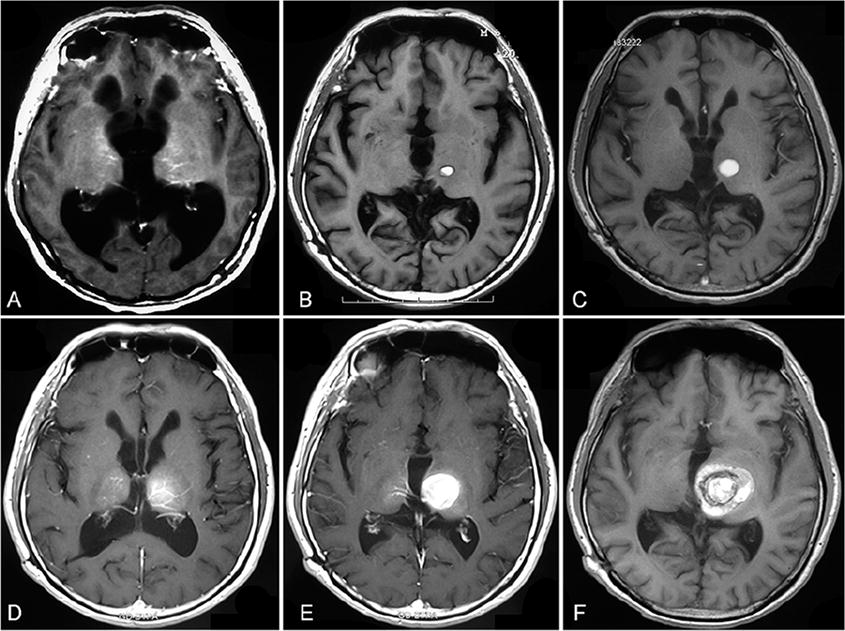

丘腦海綿狀畸形(CMs)的發(fā)病率約為0.4%至0.8%,病變通常涉及腦白質(zhì)或皮質(zhì)下丘腦也很少。由于丘腦內(nèi)和周圍存在重要的神經(jīng)血管結(jié)構(gòu),涉及這些部位的出血性發(fā)作可導(dǎo)致嚴(yán)重的神經(jīng)功能缺...

顱內(nèi)海綿狀血管瘤發(fā)病率0.4%~0.6%,腦干海綿狀血管瘤(brainstemcavemoma,BC)約占其中9%~35%。大多數(shù)腦干海綿狀血管瘤為散發(fā)和單發(fā),但報(bào)道仍有高達(dá)24%的病例為多發(fā)病灶,且均...